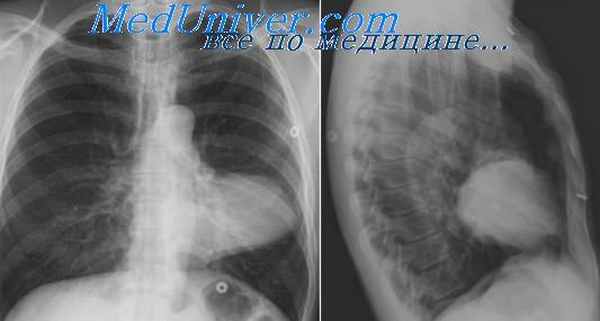

• Нейрогенные опухоли (невриномы) •• Частота. Занимают второе место среди опухолей средостения. Невриномы могут быть проявлением нейрофиброматоза (болезни фон Реклингхаузена) •• Этиология. Опухоли развиваются из нервных элементов симпатического ствола, ветвей блуждающего нерва, оболочек мозга и межрёберных нервов. Чаще располагаются в верхнем средостении •• Морфология. Шванномы, невролеммомы, ганглионевромы, нейрофибромы •• Диагноз. У большинства больных с невриномами жалоб нет. При росте опухоли в просвете спинномозгового канала (в виде песочных часов) возможна неврологическая симптоматика. Диагноз устанавливают рентгенологически, при помощи КТ органов грудной клетки. На снимках опухоли выглядят как округлые чётко очерченные тени, расположенные в области рёберно-позвоночного угла •• Лечение — торакотомия, удаление опухоли ••

В средостении наблюдается возникновение двух гистогенетических групп опухолей.

Первая группа – опухоли, происходящие из элементов собственно нервной ткани – нервных клеток и оболочек нервных волокон (нейробластомы, ганглионейробластомы, ганглионевромы, параганглиомы). Вторая группа – опухоли, происходящие из элементов оболочек периферических нервов: шванномы, нейрофибромы, злокачественные опухоли оболочек периферических нервов. Нейрогенные опухоли локализуются в заднем средостении (в костновертебральном углу) и по мере роста распространяются на боковую поверхность позвоночника и начальные отделы ребер. Новообразования могут располагаться в разных отделах средостения, на разных уровнях – от VII шейного до XI грудного позвонка, в основном с одной стороны. Но могут находиться и кпереди от позвоночника, вдаваясь в обе плевральные полости. В переднем средостении нейрогенные опухоли локализуются редко. Клиническое течение нейрогенных опухолей средостения весьма разнообразно и обусловлено их локализацией, размерами, характером роста, взаимоотношениями с окружающими тканями и органами. Основным методом диагностики нейрогенных опухолей является рентгенологическое исследование, позволяющее выявить патологическую тень в средостении. Размеры, конфигурация, локализация тени во многом обусловлены типом роста опухоли – инкапсулированным (доброкачественным) или инфильтративным (злокачественным). Все нейрогенные опухоли подлежат хирургическому удалению с последующим морфологическим исследованием. Окончательный диагноз нейрогенной опухоли верифицируется по результатам гистологического исследования.

Больной С., 21 год, поступил в отделение торакальной хирургии 301-го ОВКГ по поводу новообразования верхнего и переднего средостения. Опухоль средостения выявлена при ФОГК. При поступлении в 301-й ОВКГ больной жаловался на периодические боли за грудиной слева, иррадиирующие в левую руку. При КТ: «признаки объемного образования заднего верхнего средостения размерами 7,6×6,4×4,0 см, вероятнее всего невринома». 21.01.2010 г., интраоперационно: «опухолевидное образование в верхнем и заднем средостении, размерами 7,8×6,0×5,0 см, вдается в левую плевральную полость с продолжением до дуги аорты, отделено от костальной плевры, сосудов, органов средостения, ножка опухоли уходит вверх по позвоночнику на боковую поверхность шеи». При экспресс-биопсии исследован кусочек ткани опухоли размерами 4,0×2,5×0,7 см, мягкоэластической консистенции, желтоватого цвета. Микроскопически: при исследовании свежезамороженных срезов выявлена «опухоль в соединительнотканной капсуле, состоящая из клеток типа ганглиозных – крупных, со светлой зернистой цитоплазмой и крупными ядрами, расположенных поодиночке и группами, окруженных пучками соединительной ткани с фиброцитами, местами встречаются клетки с интенсивно окрашенными ядрами типа симпатобластов. Заключение: доброкачественная опухоль из симпатических ганглиев, наиболее вероятна – ганглионеврома». Дальнейшее исследование операционного материала: «Образование размерами 7,0×5,0×3,5 см, с гладкой поверхностью, покрытой капсулой, на разрезах ткань мягкоэластической консистенции, белесоватого цвета, дольчатая. Гистологически: опухоль представлена ганглиозными клетками, заключенными в фиброзную отечную строму, волокнистые структуры окрасились по Ван-Гизону в желтый цвет, местами отмечались ритмичные структуры, завихрения, участки миксоматоза, имелись группы мелких интенсивно окрашенных клеток типа симпатобластов; заключение: ганглионеврома».